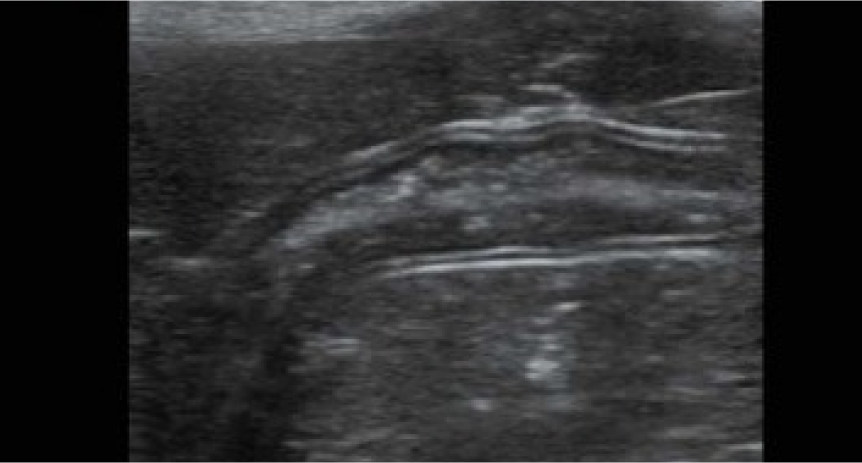

TSI Las imágenes específicas de tejido optimizan la calidad de imagen basándose en las propiedades del tejido que está siendo escaneado. Están disponibles cuatro opciones de imágenes, las cuales incluyen un imagen general, de músculos, de fluidos y grasas. Flujo de trabajo y rendimiento

TSI Las imágenes específicas de tejido optimizan la calidad de imagen basándose en las propiedades del tejido que está siendo escaneado. Están disponibles cuatro opciones de imágenes, las cuales incluyen un imagen general, de músculos, de fluidos y grasas.

Galería de imágenes

Galería de imágenes